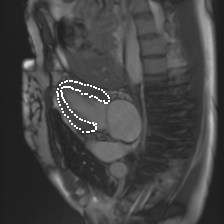

Accurate segmentation and motion estimation of myocardium have always been important in clinic field, which essentially contribute to the downstream diagnosis. However, existing methods cannot always guarantee the shape integrity for myocardium segmentation. In addition, motion estimation requires point correspondence on the myocardium region across different frames. In this paper, we propose a novel end-to-end deep statistic shape model to focus on myocardium segmentation with both shape integrity and boundary correspondence preserving. Specifically, myocardium shapes are represented by a fixed number of points, whose variations are extracted by Principal Component Analysis (PCA). Deep neural network is used to predict the transformation parameters (both affine and deformation), which are then used to warp the mean point cloud to the image domain. Furthermore, a differentiable rendering layer is introduced to incorporate mask supervision into the framework to learn more accurate point clouds. In this way, the proposed method is able to consistently produce anatomically reasonable segmentation mask without post processing. Additionally, the predicted point cloud guarantees boundary correspondence for sequential images, which contributes to the downstream tasks, such as the motion estimation of myocardium. We conduct several experiments to demonstrate the effectiveness of the proposed method on several benchmark datasets.